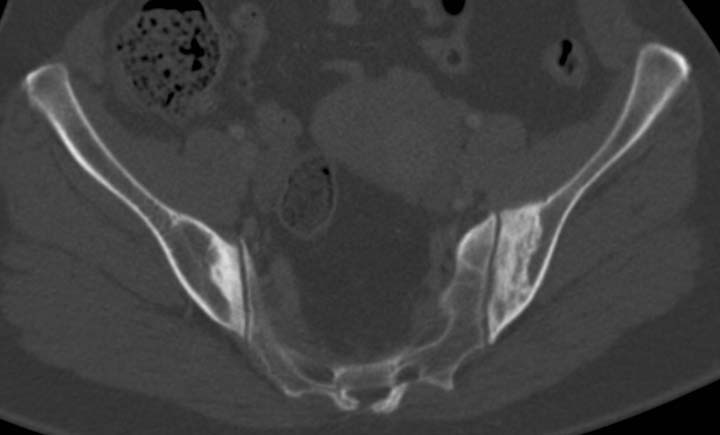

Osteitis condensans ilii is identiifed as benign sclerosis of the ilium adjacent to the sacroiliac joint. It is typically bilateral and symmetrical, and tends to be triangular in shape. This radiological abnormality is thought to be a benign reflection of bone remodelling with response to stress (increased radiologic density indicative of sclerosis) the sacroiliac joint itself is normal with no irregularity, erosions or loss of joint space.

It is most commonly seen in multiparous females; the underlying aetiology is believed to be mechanical stress across the sacroiliac joint. It is usually asymptomatic but uncommonly may cause lower back pain. The differential diagnosis is sacroiliitis, and rarely bone infection.